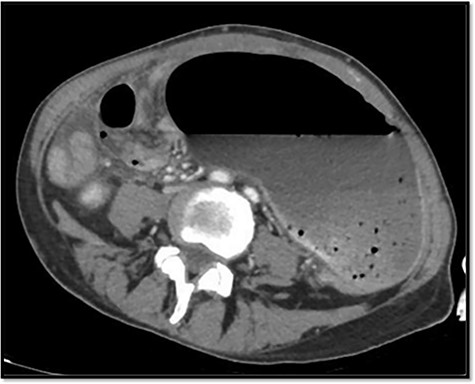

The emergency blood test showed a normochromic and normocytic anemia with an hemoglobin of 10.1 mg/dl and a leukocytosis of 11.150/ul with 70% neutrophils. The abdominal radiography showed a prominent dilation of a small bowel loop. The CT scan reported an 18-cm dilated loop. The main diagnostic suspicion was a small bowel volvulus without signs of ischemia or perforation (Figs 1–3).

With this diagnosis, an emergency laparotomy is performed. It showed a cecum volvulus that compromised 6 cm of distal ileum. The cecum was ischemic, with transmural necrosis. Ileocechectomy was performed including a 15-cm segment of distal ileum. Intestinal transit was reconstructed with mechanical latero-lateral ileo-colic anastomosis with manual reinforcement. The closure of the abdominal wall was performed with a supraaponeurotic prophylactic mesh.

However, abdominal radiographs and soluble contrasts have been relegated in favor of computed tomography. This image has a sensitivity close to 100% and a specificity of 90%. Furthermore, it allows the observation of indirect signs of complications such as necrosis or perforation [3].